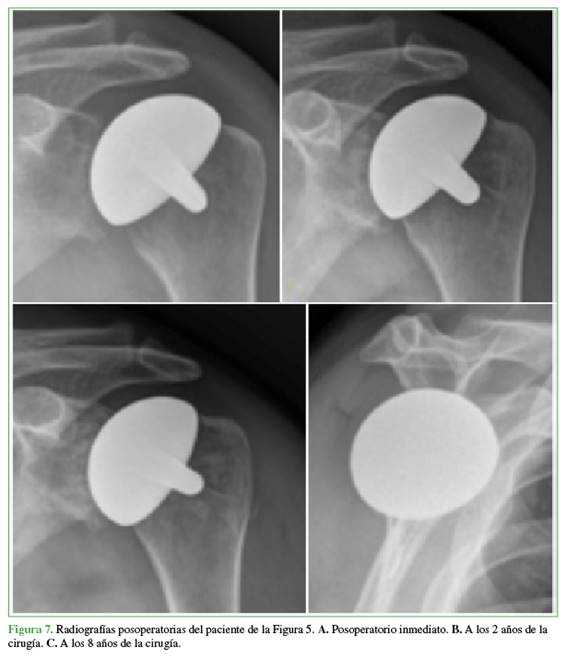

Resultados radiográficos: antes de la cirugía, los 25 hombros tenían artrosis grado 3 de la clasificación de Samilson y Prieto12 (pérdida de luz articular, quistes y osteofitos) (Figuras 6 y 7).

Hubo 7 casos de desgaste asimétrico de la glenoides (4 tipo B1 y 3 tipo B2 de Walch13). Además, 7 hombros tenían una subluxación moderada y 1, una severa. Tras la cirugía, la subluxación se resolvió en 22 hombros y persistió levemente en 3 pacientes. El espacio articular glenohumeral promedio aumentó de 1,2 mm (rango 0-3) antes de la operación a 3,4 mm (rango 1-5) después. La TC de control reveló una disminución del espacio articular por desgaste del alomenisco, correlacionado con el tiempo de evolución (Figura 8). Para una evaluación más detallada de la erosión glenoidea posoperatoria, se analizaron las TC de seguimiento en el último control. Se clasificó la erosión glenoidea de la siguiente manera: 15 pacientes (60%) tenían erosión mínima o nula; 7 (28%), erosión moderada y 3 (12%), erosión severa. Estos hallazgos cualitativos confirman la progresión del desgaste glenoideo a largo plazo, a pesar de la interposición meniscal, la erosión fue una complicación esperada. En cuanto a los hallazgos intraoperatorios relevantes, en 2 pacientes con antecedentes de luxofractura de húmero, se reparó el manguito rotador con puntos de suturas no reabsorbibles. Uno de ellos tenía una lesión del supraespinoso y otro, del subescapular. Cinco tenían cuerpos libres articulares en cantidad variable.1-3 No se registraron infecciones. Se observó un hematoma posoperatorio no complicado en un paciente y un resultado funcional pobre, pero con franca mejoría del dolor en una mujer con antecedente de osteonecrosis por luxofractura de húmero.